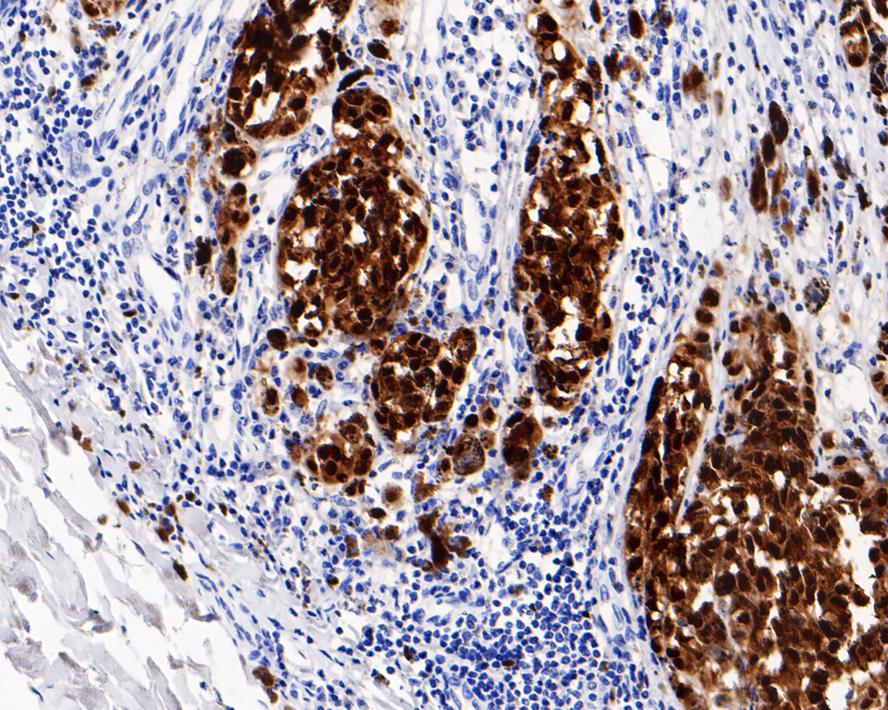

Immunohistochemical analysis of paraffin-embedded human malignant melanoma tissue with Rabbit anti-SOX10 antibody (HA721240) at 1/3,000 dilution.

The section was pre-treated using heat mediated antigen retrieval with sodium citrate buffer (pH 6.0) (high pressure) for 2 minutes. The tissues were blocked in 1% BSA for 20 minutes at room temperature, washed with ddH2O and PBS, and then probed with the primary antibody (HA721240) at 1/3,000 dilution for 1 hour at room temperature. The detection was performed using an HRP conjugated compact polymer system. DAB was used as the chromogen. Tissues were counterstained with hematoxylin and mounted with DPX.